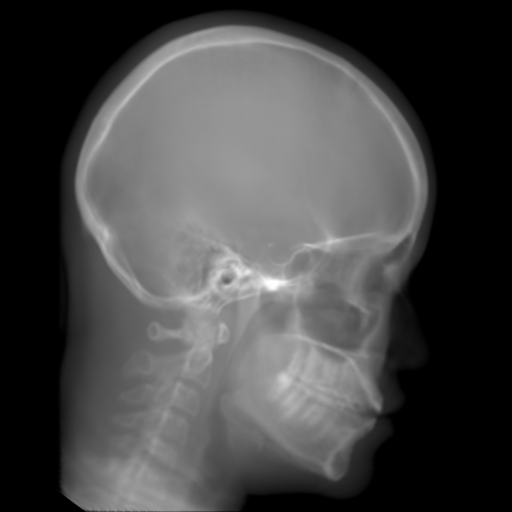

5.2 Head Data

Refer to caption

(a) Reference

(b) 0superscript00^{\circ} perspective

(c) (b)-(a)

7.80, 0.9093

Pix2pixGAN Prediction

(d) 0superscript00^{\circ} Cartesian

(e) 0&180superscript0superscript1800^{\circ}\&180^{\circ} Cartesian

(f) 0&180superscript0superscript1800^{\circ}\&180^{\circ} polar

6.06, 0.9249

2.99, 0.9820

2.07, 0.9842

Pix2pixGAN difference

(g) (d)-(a)

(h) (e)-(a)

(i) (f)-(a)

TransU-Net Prediction

(j) 0superscript00^{\circ} Cartesian

(k) 0&180superscript0superscript1800^{\circ}\&180^{\circ} Cartesian

(l) 0&180superscript0superscript1800^{\circ}\&180^{\circ} polar

6.45, 0.9356

2.36, 0.9864

3.65, 0.9734

TransU-Net Difference

(m) (j)-(a)

(n) (k)-(a)

(o) (l)-(a)

Figure 11: Perspective deformation learning in one exemplary patient case for cephalometric imaging. In (b), the left and right sides of the mandible do not overlap well, as indicated by the arrow. In (c), a scale bar of 2 mm is displayed (zoom in for better visualization), as 2 mm is the clinically acceptable precision for cephalometric landmark detection. In (e), (h) and (j), incorrect areas are marked by the red arrows.

TABLE III: Quantitative evaluation of different methods on head data.

Method Metric 0superscript00^{\circ} input 0superscript00^{\circ} 0&180superscript0superscript1800^{\circ}\&180^{\circ} 0&180superscript0superscript1800^{\circ}\&180^{\circ}

perspective Cart. Cart. polar

Pix2pix RMSE 10.69 7.33 4.58 3.87

GAN SSIM 0.8680 0.9053 0.9476 0.9625

Trans RMSE 10.69 8.13 3.36 3.22

U-Net SSIM 0.8680 0.9257 0.9682 0.9719

The results of one exemplary patient for cephalometric imaging are displayed in Fig. 11. In the 0superscript00^{\circ} perspective projection image (Fig. 11(b)), because of perspective deformation, anatomical structures from the left and right sides do not overlap well, especially for the mandible as indicated by the red arrow in Fig. 11(b). It causes inaccuracy in determining the cephalometric landmark of the gonion. The difference of Fig. 11(b) to the reference Fig. 11(a) is displayed in Fig. 11(c). A scale bar of 2 mm is displayed in Fig. 11(c), as 2 mm is the clinically acceptable precision for cephalometric landmark detection. It is obvious that many anatomical structures in the 0superscript00^{\circ} perspective projection images have position shifts larger than 2 mm. In the prediction image (Fig. 11(d)) using a single 0superscript00^{\circ} view in Cartesian coordinates, perspective deformation is reduced to some degree, as displayed in the difference image Fig. 11(g). For example, the mandible region has less error. However, Fig. 11(g) also indicates that many bony structures still have deviations larger than 2 mm. The results of learning from dual complementary views in Cartesian and polar coordinates are displayed in Fig. 11(e) and Fig. 11(f), respectively. Both images have little perspective deformation, as revealed by their difference images in Fig. 11(h) and Fig. 11(i). Nevertheless, in Fig. 11(e), two dark regions are indicated by the two arrows, which are better visualized in the difference image Fig. 11(h). The results of TransU-Net are displayed in Figs. 11(j)-(o). In Fig. 11(m), the structures near the porion landmark are distorted, for example, the ear canal indicated by the arrow. Consistent with Pix2pixGAN, perspective deformation is largely reduced in the both TransU-Net prediction images using dual complementary views in Cartesian and polar coordinates.